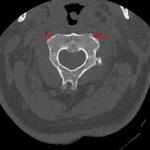

- Acute minimally displaced fracture through the anterior superior corner of the left C2 lateral mass

- Adjacent coronally oriented fracture line extends through the anterior C2 vertebral body cortex without propagation into the odontoid

- Mild anterolisthesis of C2 on C3

- Acute minimally displaced C2 fracture

Acute minimally displaced fracture through the anterior superior corner of the left C2 lateral mass. Adjacent coronally oriented fracture line extends through the anterior C2 vertebral body cortex without propagation into the odontoid.

Mild anterolisthesis of C2 on C3 is favored degenerative in etiology given multilevel advanced spondylosis and degenerative facet disease without convincing evidence of traumatic malalignment.